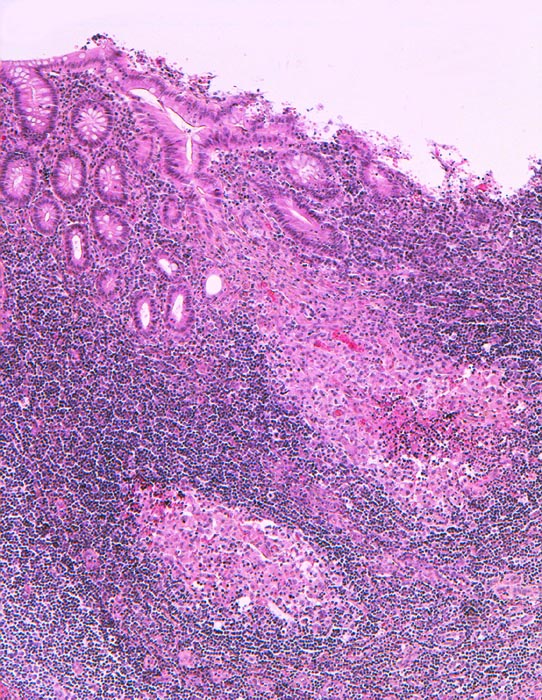

PathoPic – image database / PathoPic ID 1223 - Retikulozytär abszedierende Entzündung bei Yersiniose

Retikulozytär abszedierende Entzündung bei Yersiniose

Appendix vermiformis

Ansammlung von Histiozyten mit zentraler granulozytärer Abszedierung im Stroma der Mucosa. Das Epithel ist intakt.

Eitrige Peritonitis.

Der histologische Befund ist charakteristisch aber nicht beweisend für eine Yersiniose. Dazu braucht es den zusätzlichen Nachweis von Yersinia pseudotuberculosis im Stuhl oder serologisch. Typisch ist die mesenteriale Lymphadenitis.